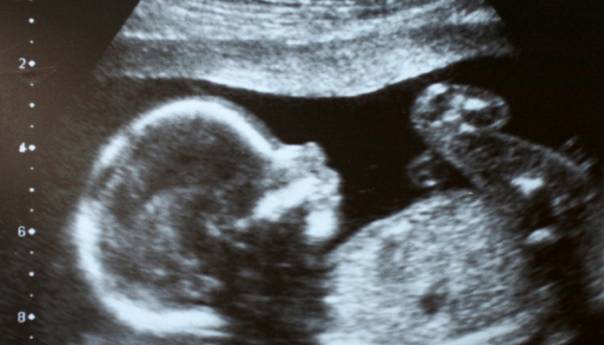

Pretpostavka da je maternica sterilno okruženje i da bebe razvijaju mikrobiom, tj. zajednicu crijevnih bakterija i drugih mikroorganizama, tek nakon rođenja, jedan je od utvrđenih principa imunologije i reproduktivne biologije. Nekoliko studija objavljenih od 2010. dovodi u pitanje ovaj princip nakon što su bakterije pronađene u uzorcima placente i amnionske tekućine.

Interdisciplinarni tim vodećih stručnjaka za istraživanje mikrobioma iz područja reproduktivne biologije, embriologije i imunologije pomno je pregledao ove konfliktne studije i verifikovao analize. Nakon pregleda studija i vlastite analize, naučnici su utvrdili da je do otkrivanja mikrobioma u fetalnom tkivu došlo zbog kontaminacije uzoraka uzetih iz maternice.